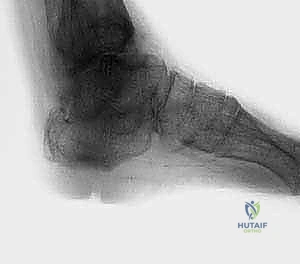

2. التصوير الطبي المتقدم

- الأشعة السينية (X-rays) أثناء الوقوف: وهي الخطوة الأهم لرؤية العظام تحت تأثير وزن الجسم. تظهر الأشعة اختفاء المسافة المفصلية، وتكوّن النتوءات العظمية، ودرجة التشوه المحوري.

- الأشعة المقطعية (CT Scan): ضرورية جداً لتقييم جودة العظام بشكل ثلاثي الأبعاد، وتحديد مدى التجاويف العظمية (Cysts) التي قد تحتاج إلى ترقيع عظمي أثناء الجراحة.

في الحالات المرضية المتقدمة التي يستهدفها هذا المقال، يكون التلف قد طال كلا المفصلين. الألم لا يأتي فقط من حركة القدم لأعلى ولأسفل، بل أيضاً من أي محاولة للتكيف مع الأرض. الغضاريف التي كانت تعمل كوسائد ملساء قد اختفت تماماً، والعظام قد تشوهت، وتكونت نتوءات عظمية (Osteophytes) تزيد من تقييد الحركة وتضاعف الألم.

يُعد هذا هو السبب الأكثر شيوعاً. التعرض لكسر شديد في الكاحل أو عظمة الكعب في الماضي (حتى لو كان قبل 10 أو 20 عاماً)، أو تمزقات الأربطة المتكررة التي لم تُعالج بشكل صحيح، يؤدي إلى تغيير في الميكانيكا الحيوية للمفصل. هذا الخلل يؤدي إلى تآكل الغضاريف بشكل غير متساوٍ ومسارع. - النخر اللاوعائي لعظمة الكاحل (Avascular Necrosis of the Talus):

عظمة الكاحل (Talus) تتميز بخصائص تشريحية فريدة، حيث أن ترويتها الدموية محدودة وهشة. إذا انقطع الدم عن هذه العظمة (بسبب كسر، خلع، أو استخدام مفرط للكورتيزون)، تموت أنسجة العظمة وتنهار. انهيار عظمة الكاحل يدمر مفصل الكاحل أعلاها والمفصل تحت الكاحل أسفلها في وقت واحد. - اعتلال المفاصل العصبي (Charcot Arthropathy):